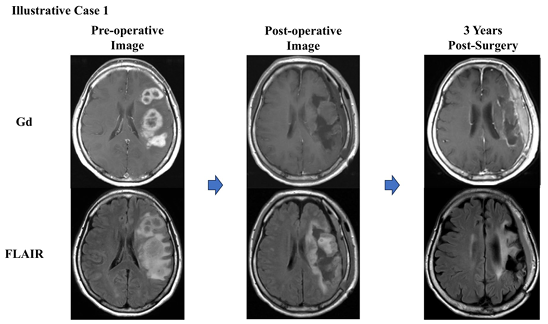

右半盲(右側視野が見えない)の59歳女性の例も紹介されています(Koriyama et al. 2025) 。

診断と治療経過:

MRIで左後頭葉に造影剤反応を示す病変が確認されました。

他の施設で腫瘍を完全切除(GTR)した後、放射線治療、化学療法(TMZ)、そして自家がんワクチン(AFTV)療法が行われました。

再発とその後の治療:

初回治療後6か月以内に再発が確認され、再度腫瘍切除が行われました。再発部位には光線力学療法(PDT)も併用されました。

さらに6か月後に再発し、再度腫瘍切除が行われましたが、この時点では病理学的に腫瘍細胞はほとんど見られず、主に壊死組織が確認されました。

出典: Koriyama, S. et al., 2025. Brain Tumor Pathology, 42:76–86, Fig. 3. CC BY 4.0. 詳細はPubMedをご参照ください。

治療結果:

- 7年間再発なしで経過観察中

- 総生存期間は8年間

- Karnofsky Performance Status(KPS)80を維持

- AFTV療法により、再発後にも免疫応答が働き、遅発性の治療効果を発揮

免疫微小環境

共通所見: CD3+・CD8+T細胞は浸潤していたが、CD4+T細胞は稀。

PD-L1陽性例: CD4陽性細胞の増加傾向 → Tregの関与が示唆。

この症例は、AFTV療法が早期再発例においても有効性を示し、標準治療では対応が難しい残存腫瘍や微小病変に対しても長期にわたり制御効果を発揮する可能性があることを示しています。